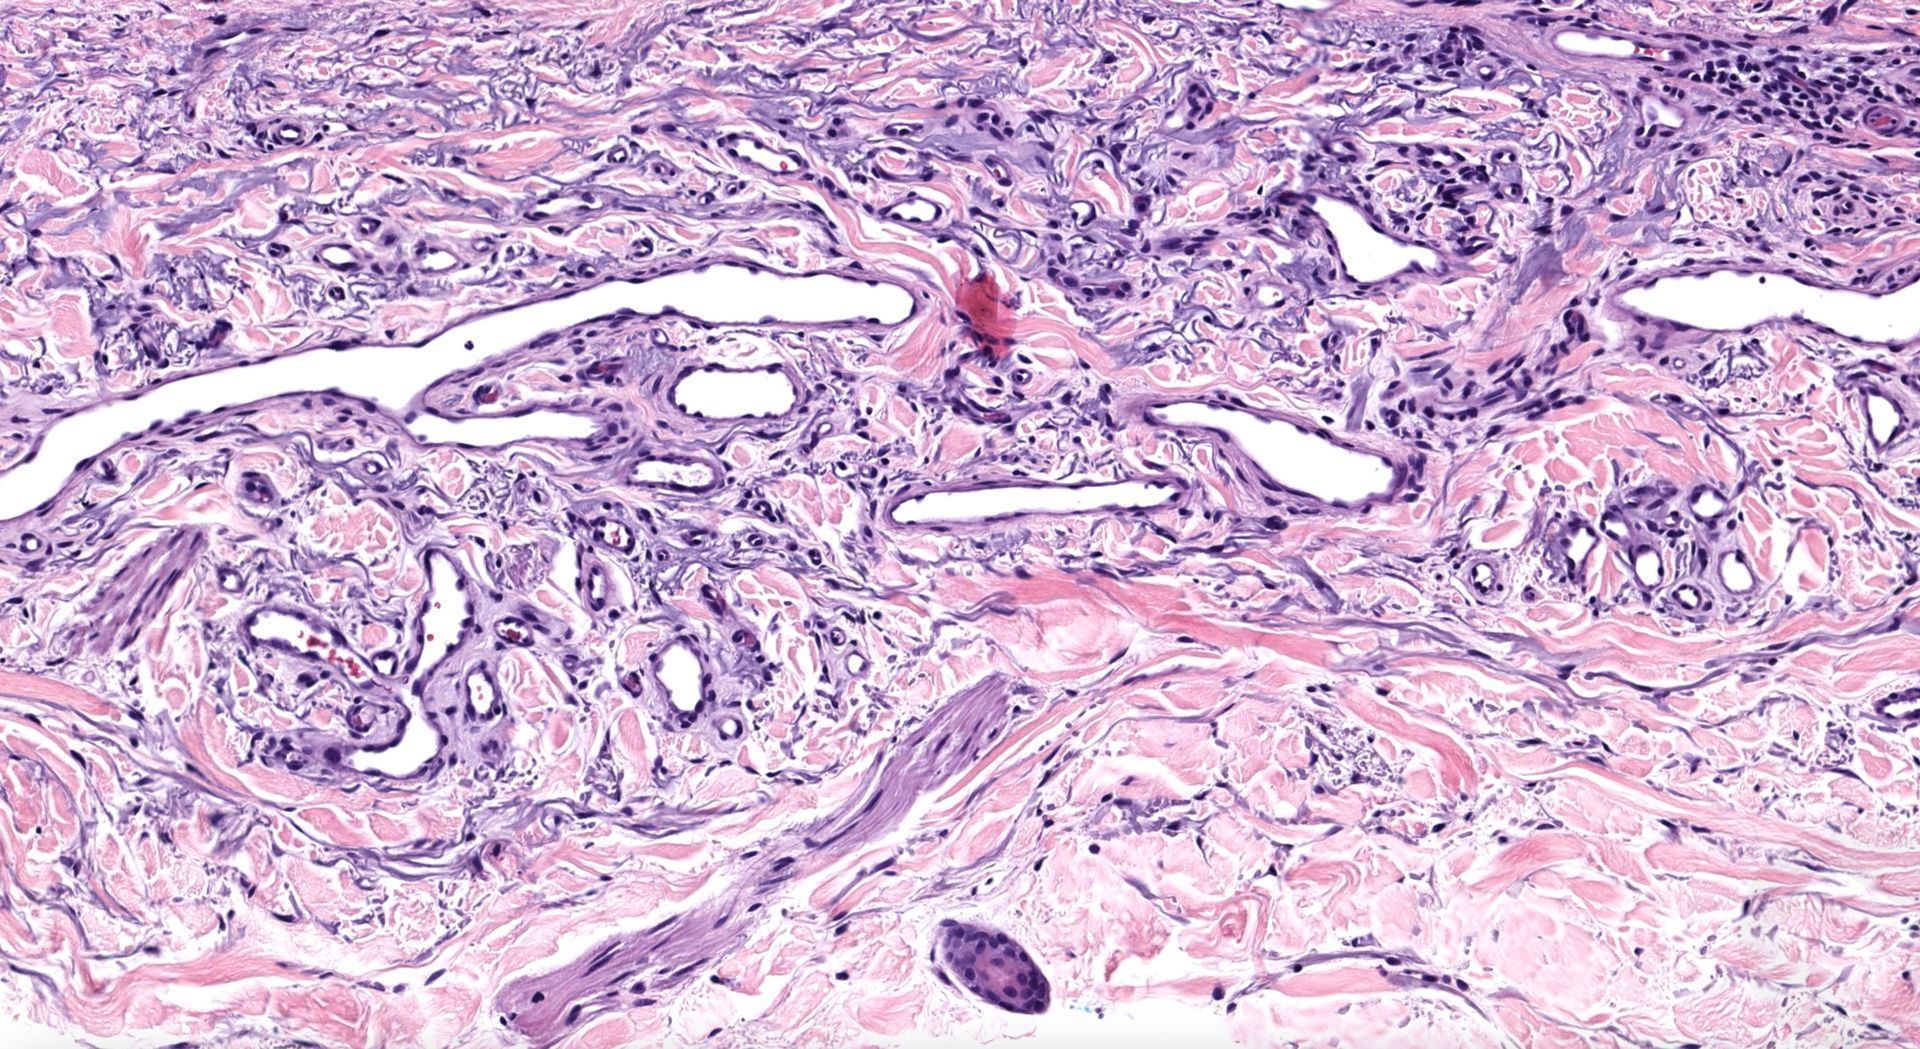

What process is happening here? How old is this patient?